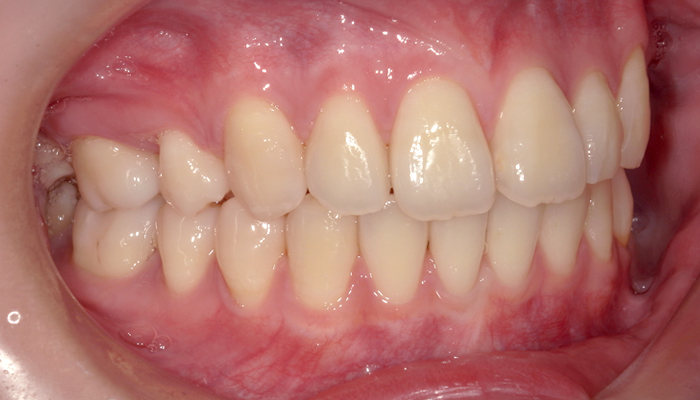

正面 治療前

正面 治療後

年齢・性別 | 20代・女性 |

---|---|

主訴 | 矯正治療希望 |

治療内容 | ワイヤー矯正 |

費用 | ワイヤー矯正 ¥770,000 |

期間 | 約2年 |

副作用・リスク | しみたり、違和感を感じたりすることがあります。 |

担当者所見 | 矯正治療を希望されて来院しました。顔貌、口元から比較すると、治療前は上顎前歯部が前方に出ていました。 上顎左右小臼歯の抜歯を行い、矯正治療にて上顎前歯部を内側に入れていき、治療後は上顎前歯部の被蓋関係も良好になりました。口元もきれいなスマイルになり、口唇も閉じやすい状況に変化しています。 |